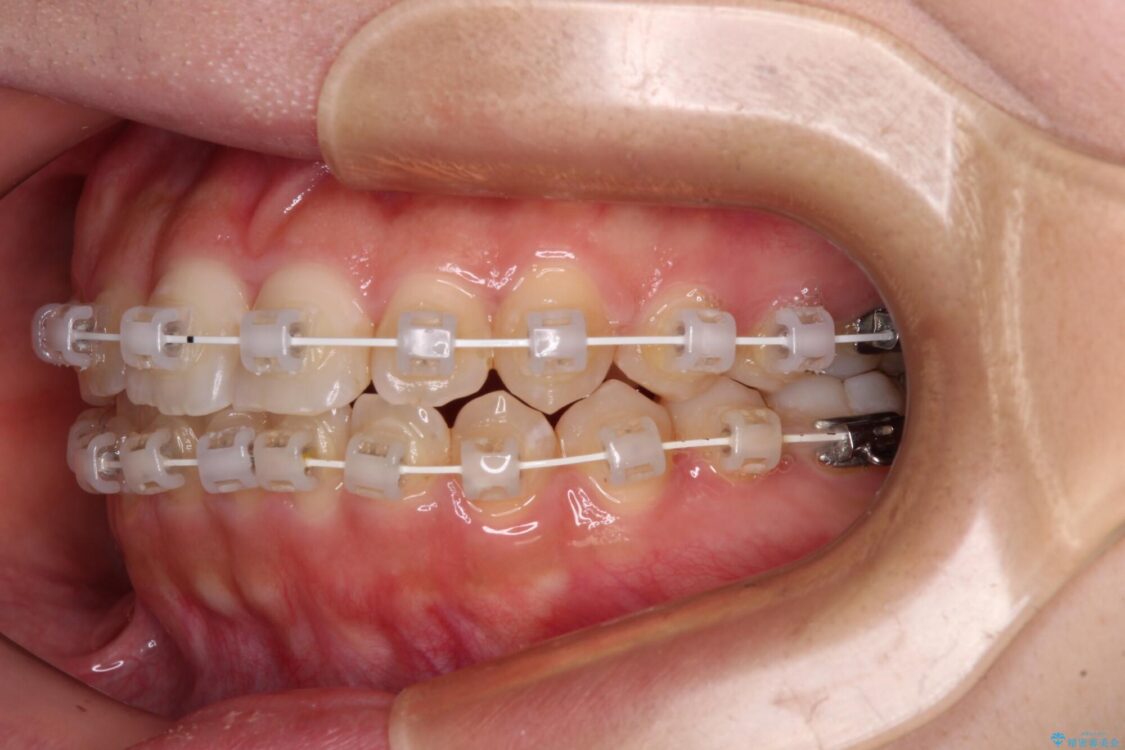

治療途中

• 【モニター】短期間で終わりたい ワイヤー装置での非抜歯矯正 治療途中画像